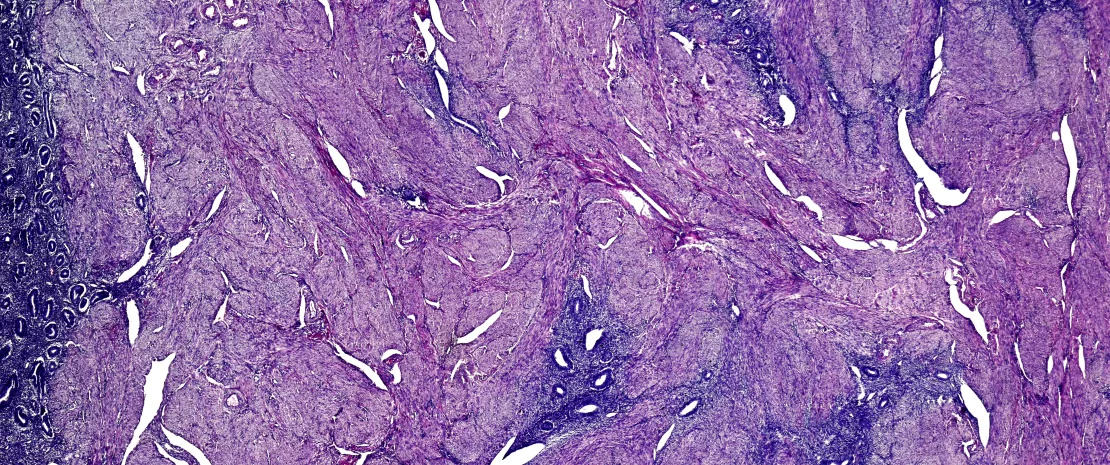

L'endométriose touche environ 10 % des femmes en âge de procréer avec des symptômes comme la dysménorrhée, la dysurie, des douleurs pelviennes et une baisse de la fertilité voire une infertilité.

L’un des diagnostics, invasif (cœlioscopie), retarde la prise en charge. D’où l’espoir de trouver un jour un marqueur non invasif.